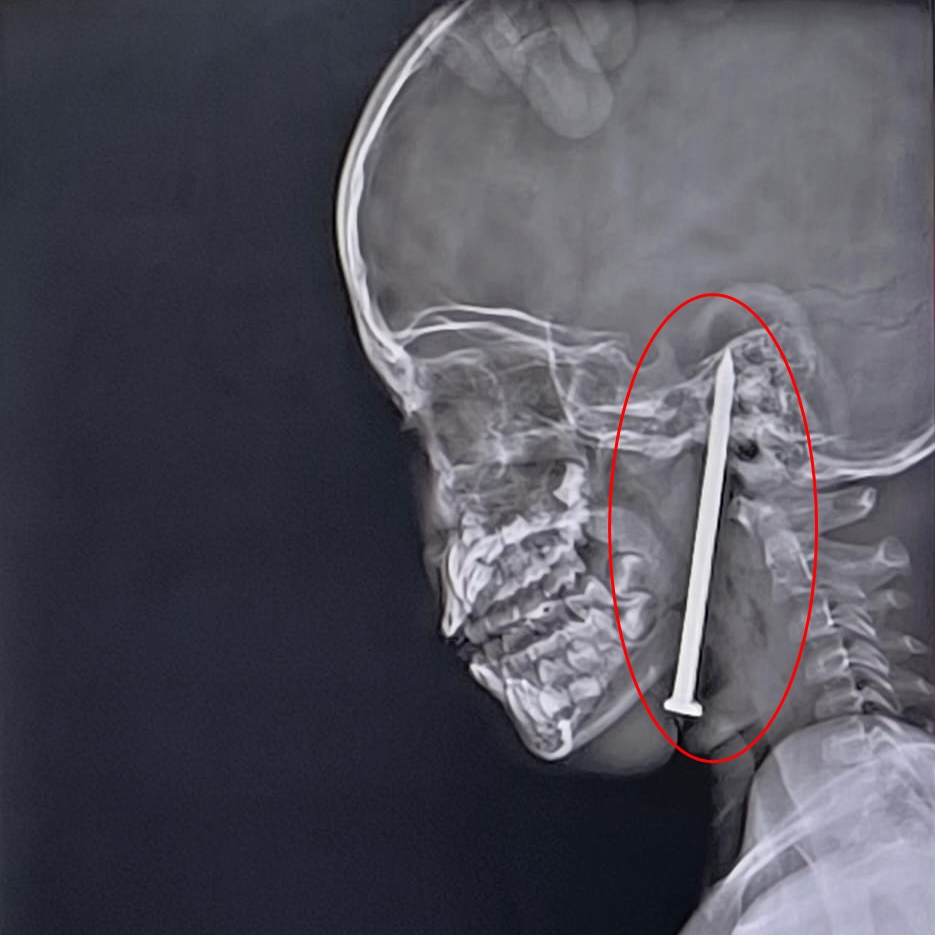

V Indiji se je zgodila grozljiva nesreča. Sedemletni deček je med igro padel na osem centimetrov dolg žebelj, ki mu je prebodel glavo. Sledila je zahtevna deseturna operacija.

Sedemletni deček iz okrožja Balrampur v indijski zvezni državi Uttar Pradesh je med igro padel na osem centimetrov dolg žebelj, ki se mu je zaril v glavo, poročajo indijski mediji.

Družina ga je nemudoma odpeljala v lokalno bolnišnico, vendar se je njegovo stanje kmalu poslabšalo, zato so ga premestili v večji travmatološki center v mestu Lucknow. Tamkajšnji zdravniki so opravili MRI- in CT-preiskave, ki so pokazale, da je osem centimetrov dolg žebelj nevarno prebil večjo žilo v njegovih možganih.

Z mikrokirurškimi tehnikami in sodobno nevronavigacijo so žebelj uspešno odstranili, ne da bi pri tem poškodovali možgane. Deček tako ni več v smrtni nevarnosti in že okreva, še poroča India Today.